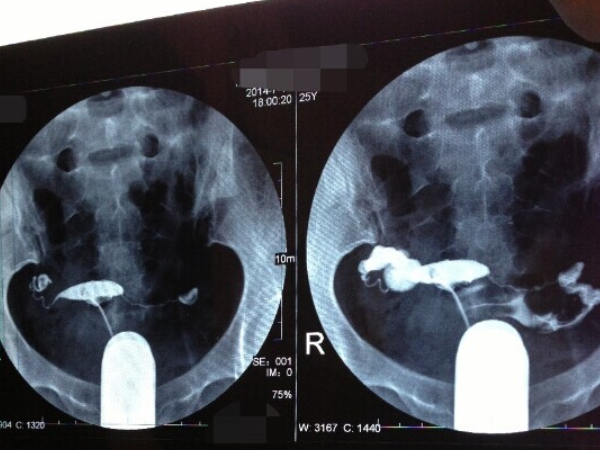

输卵管积水的严重程度不同,试管移植前抽取手术的时间也会有所区别。对于积液直径小于1cm和输卵管伞端完好的患者,一般在试管婴儿移植前1-2天进行手术。对于直径大于3cm和伞端完全被包埋的患者,一般在试管婴儿移植前3天进行手术。因此,患者需要积极配合医生进行治疗,将里面的积水尽可能的抽完,从而提高试管移植后的成功率。试管移植前几天抽积水好所谓的输卵管积水其实就是在输卵管炎以后,因粘连、闭锁、黏膜细胞分...